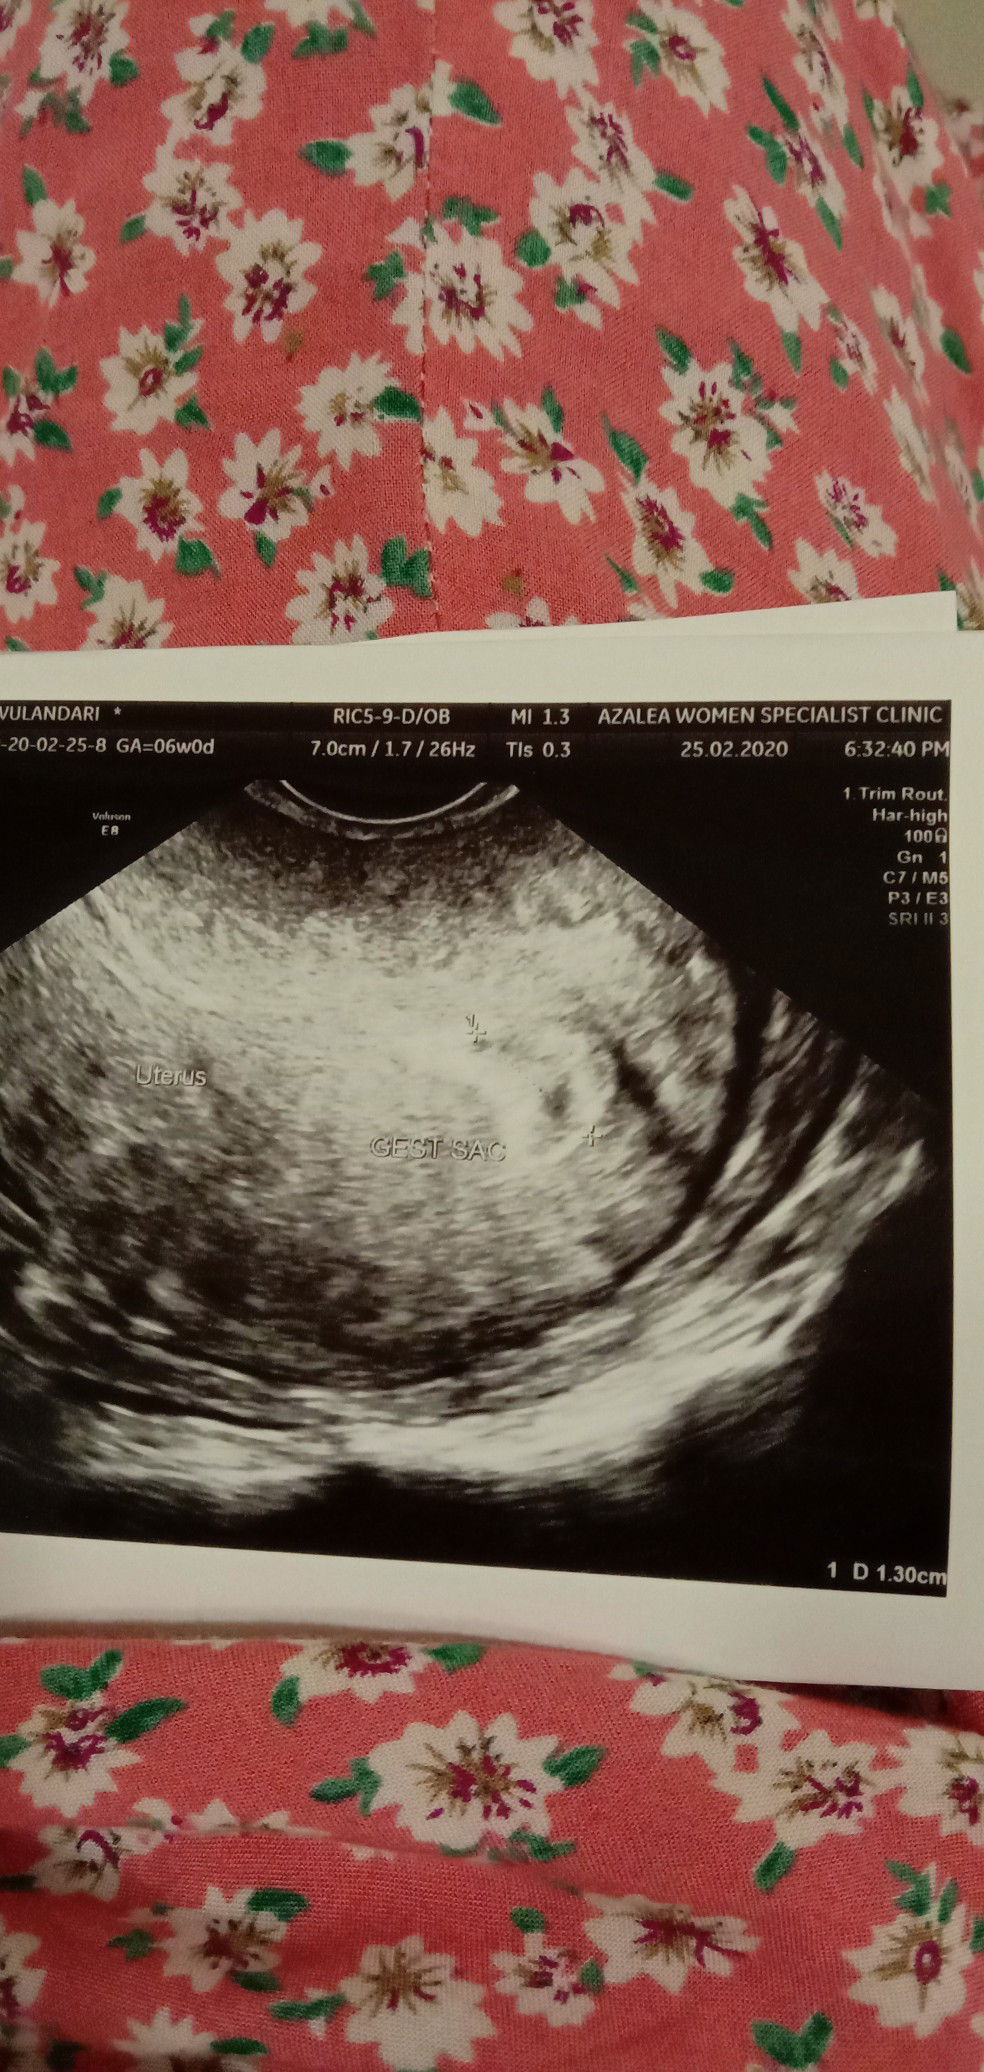

Hai momy momy ada gak yg mempuanyai kes macam saya? hari tu saya scan masa 4 week karena saya nampak ada darah so saya takut ada apa2,masa scan doktr cakap ni bleding tak apa2 ni hanya proses inplantsi dia cakap mcm tu,dia cek semua oke ada kantung tp baby blm nampak lagi dokter suru saya balik lagi 2minggu lagi.. Nah masa saya tunggu sampai usia kandungan 6 minggu saya masih keluar darah macam haid ... Lepas tu saya scan masa usia 6 minggu Dan dokter cakap kantung masih ada tp janin blm nampak saya sudah mulai wory?? Lepas tu dr cek lagi pakai trans vagian dr mau cek kenpa masih pendarahan padahal sudah di kasih obat penguat rahim... Masa dr cek dia nampak ada pebroid di dekat rahim dia kata ni yg menyebabkan sya pendarahan.. Tapi dr kata ni tak bahayakan janin selagi ukuran dia masih kecil... Dan dr minta saya balik cek lagi 10/3/2020 mau tau janin tu berkembang taw tak.. Ya allah saya ni bingung klw macam ni takut tp tak tau mau buat apa,berserah saja pada allah semoga semua baik baik saja masa scan berikutnya.. Kira kira ada tak momy momy yg mengalami macam saya klw ada boleh kongsi Saya konsi gambar scan cm ada kantong saya dan hasil darah pun saya masih + pregnn

Asalamualaikum semua mommy mommy Saya pregnn 6 week kemarin saya pergi dokter tuk rpt scan dan cek knp masih bleding sudah lama macam ni Masa scan doc cakap kantung baby ada tp blm nampak beby ada kat dlm ?? Lepas tuk doc cek kenapa masih bleding padahal sdah d kasih obat penguat rahim Maca cek doc nampak pebroid d luar rahim ini yang menyebabkan bleding tak henti Doc kata ini tak bahaya tuk janin tapi saya worry dan tak tau harus buat apa. Doc cakap sya harus bedrest total Dan dia kasih obat lagi tuk darah kurang tp blm kurang lagi.. Saya sangat worry apakan ada mommy yg mengalami sama macam kes saya..